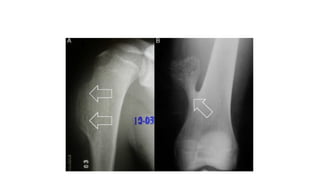

• Extremities – Involves metaphysis or diaphysis ; expansile lytic lesion

with size > 2 cm and thin peripheral cortical rim